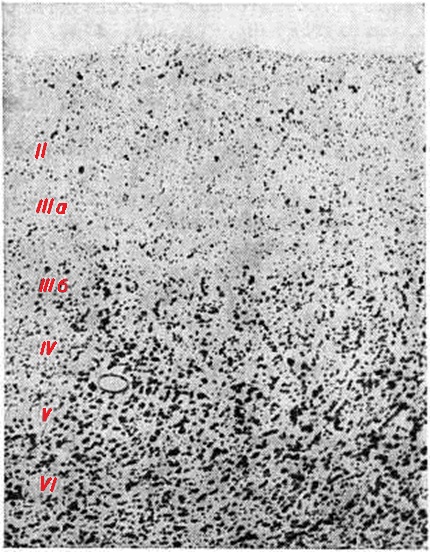

Гистологически отмечаются прогрессирующие хронический дистрофические изменения нервных клеток в виде сморщивания, атрофии, липофусциновой дегенерации, заканчивающиеся цитолизом (смотри полный свод знаний) и приводящие к резкому диффузному, а иногда и очаговому опустошению, которое сопровождается выраженным заместительным глиозом за счёт пролиферации в основном астроцитов и олигодендроглиоцитов (смотри полный свод знаний Глиоз). Клеточное опустошение особенно заметно в верхних слоях (II — III а) коры мозга (рисунок 2). Характерные признаки Пика болезнь — появление набухших баллоновидных клеток с центральным хроматолизом и эктопией ядра (рисунок 3, а), напоминающих нейроны с первичным раздражением при аксональной реакции, иногда превращающиеся в сверх набухшие гомогенизированные клетки, а также появление нейронов с аргентофильными цитоплазматическими шаровидными включениями — тельцами Пика (рисунок 3, б). По данным Эскуролля (R. Escourolle, 1956), набухшие клетки встречаются приблизительно в 60% случаев Пика болезнь, тогда как аргентофильные включения — в 20%. Преимущественная локализация набухших клеток — III — V слои коры, нейронов с аргентофильными включениями — чаще всего гиппокамп. Однако эти изменения могут встречаться во всех образованиях мозга, подвергшихся атрофии, и даже в клетках ствола мозга.

Электронно-микроскопическая картина набухших клеток и нейронов с аргентофильными включениями характеризуется по-разному. Одни исследователи не находят ультраструктурных различий между этими двумя видами поражения нейронов, другие указывают, что аргентофильные включения образованы беспорядочными сетями пролиферирующих нейрофиламентов и гранул липофусцина, а ультраструктура цитоплазмы набухших нейронов представлена обширными зонами, содержащими гранулярный материал, рассеянные нейротрубочки и изменённые митохондрии при почти полном отсутствии нейрофиламентов (смотри полный свод знаний Нервная клетка).